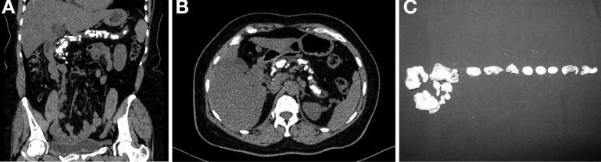

- Sỏi tụy: chụp cắt lớp vi tính là biện pháp tốt nhất để xác định sỏi tụy. Sỏi kích thước trên 1mm có thể thấy thấy trên phim chụp CLVT, sỏi xuất hiện trong nhu mô hoặc trong ống tụy hoặc ở cả nhu mô tụy và ống tụy.

- Giãn ống tụy chính: ống tụy có thể nhìn thấy khi đường kính > 3mm trên phim chụp với các lớp cắt mỏng. Nét đặc trưng của giãn ống tụy trong VTM là giãn không đều, có nhiều đoạn hẹp xen kẽ các đoạn giãn, tạo hình ảnh như tràng hạt.

- Nang giả tụy: biểu hiện bởi những cấu trúc giảm tỷ trọng (0-20HU), ranh giới rõ, nằm trong nhu mô tụy hoặc các vị trí ngoài tụy, không ngấm thuốc sau tiêm. Nếu Nang giả tụy có biến chứng Chảy máu trong nang hoặc nang bị bội nhiễm thì tỷ trọng trong nang có thể cao hơn.